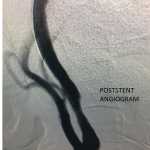

Figure 3.

Catheter angiography prior to angioplasty revealed critical stenosis (Figure 2). Angioplasty was therefore performed under local anesthesia with an embolic protection device deployed to catch any dislodged debris (Figure 3). After angioplasty, a stent was opened across the lesion to maintain long-term patency (Figure 4). Post-stent angiography showed smooth dilatation of the lesion. The patient’s aphasia continued to improve at his 6-week follow-up visit and duplex revealed no significant stenosis through the stent.